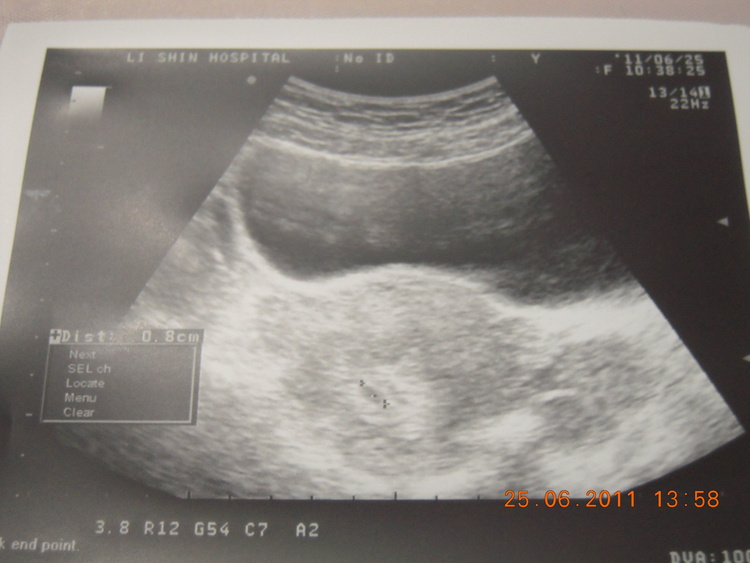

我今天5W2D

照出來是0.8cm

這樣寶寶是不是長得比較慢呢?

我在其它討論看到有人五週就1公分多了@@

今天是:民國100年6月25日--預產期是:民國101年2月23日,目前懷孕為1個多月,或懷孕5週又2天. 還有243天您就要當媽媽了,可能的受孕日在民國100年6月3日附近幾天,寶寶可能血型為:O